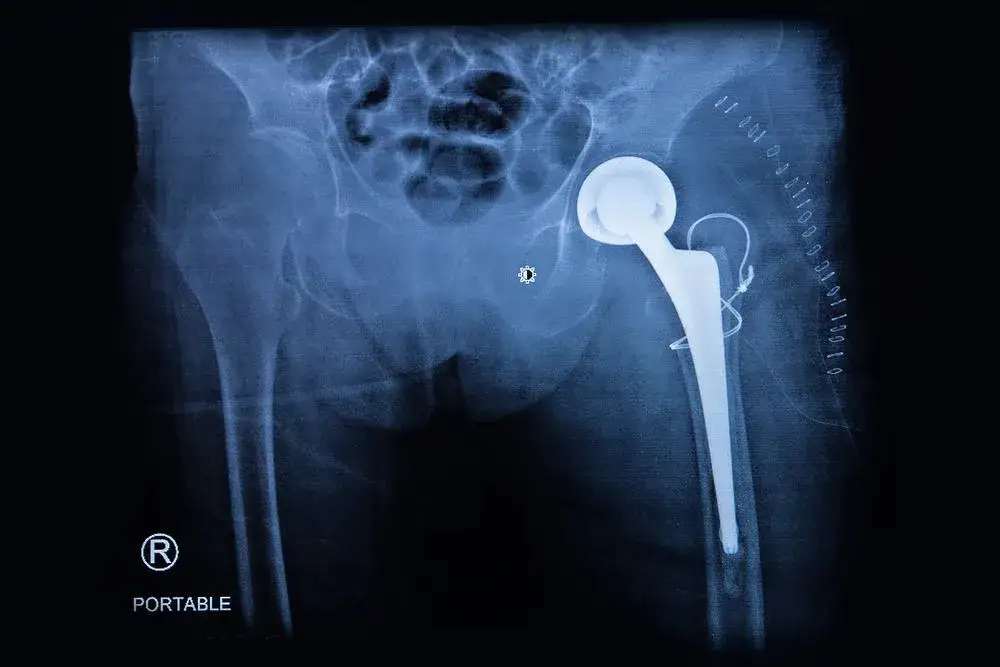

Ból po endoprotezoplastyce biodra to naturalny element procesu rekonwalescencji, który może trwać od kilku dni do kilku tygodni. W pierwszych dniach po zabiegu ból jest zazwyczaj najbardziej intensywny, a następnie stopniowo się zmniejsza. W większości przypadków pacjenci mogą oczekiwać, że dyskomfort ustąpi w ciągu 2–6 tygodni, jednak niektórzy mogą odczuwać ból nawet przez kilka miesięcy. Długość trwania bólu zależy od wielu czynników, takich jak wiek pacjenta, ogólny stan zdrowia oraz rodzaj zastosowanej endoprotezy.

Warto pamiętać, że odpowiednia rehabilitacja odgrywa kluczową rolę w zmniejszaniu bólu i przyspieszaniu procesu regeneracji. W tym artykule przyjrzymy się typowym okresom bólu po endoprotezoplastyce biodra, czynnikom wpływającym na jego długość oraz metodom łagodzenia dyskomfortu, aby pomóc pacjentom lepiej zrozumieć, czego mogą się spodziewać po zabiegu.